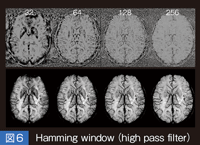

中枢神経の髄鞘から直接NMR信号を検出することは、通常の撮像法ではほぼ不可能だが、プロトン密度、T1緩和、T2緩和を駆使することによって髄鞘以外の構造のコントラストを取得し、その影絵として髄鞘密度に依存するコントラストを得ることができる。特に、プロトン密度強調画像とSTIR像では明瞭であり、T2強調画像とSTIR像との比較では、脳内のコントラストがまったく違うことがわかる( 図1)。これは、STIRではプロトン密度、T1、T2緩和が、コントラストに相加的に作用する唯一の撮像法であることに基づいていると考えられる。

図1